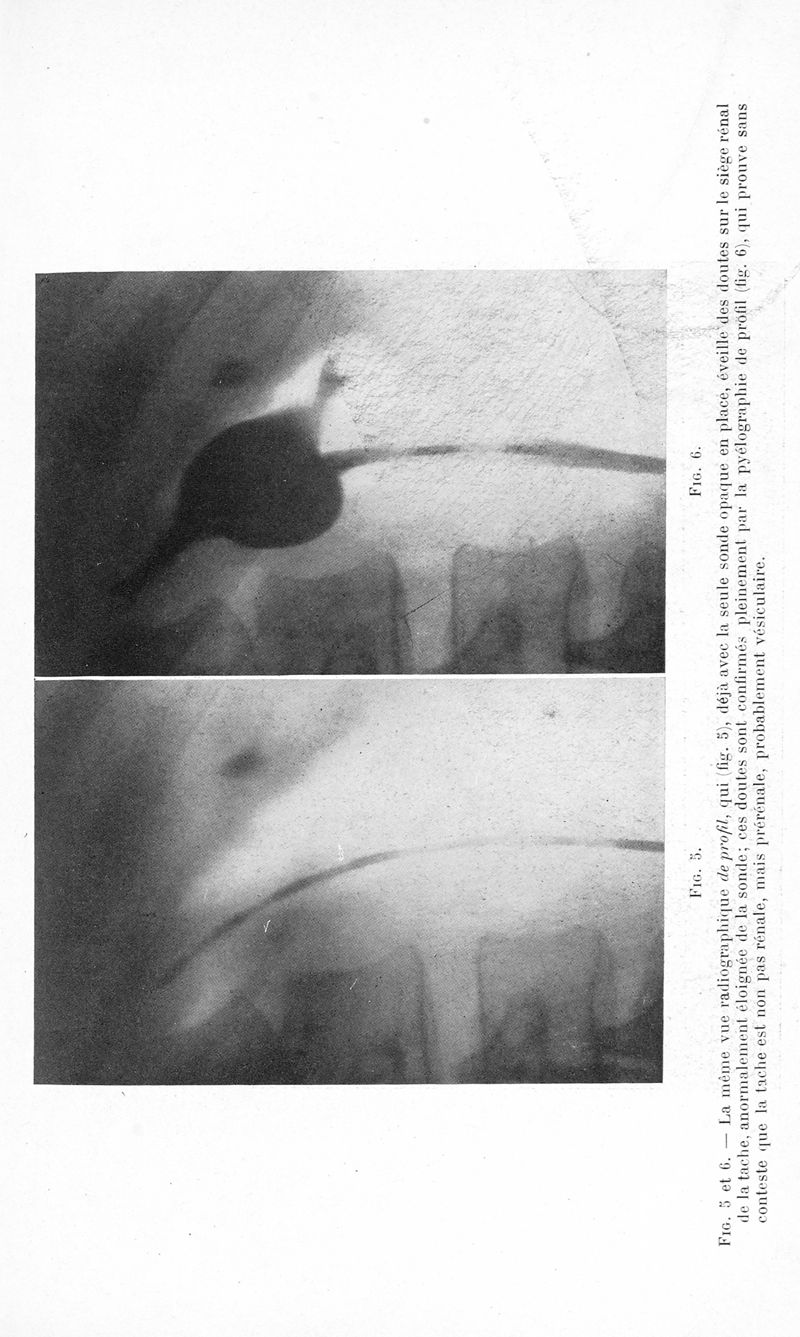

Bulletins et mémoires de la société nationale de chirurgie

Tome LXI, 1935. - Paris : Masson, 1935.